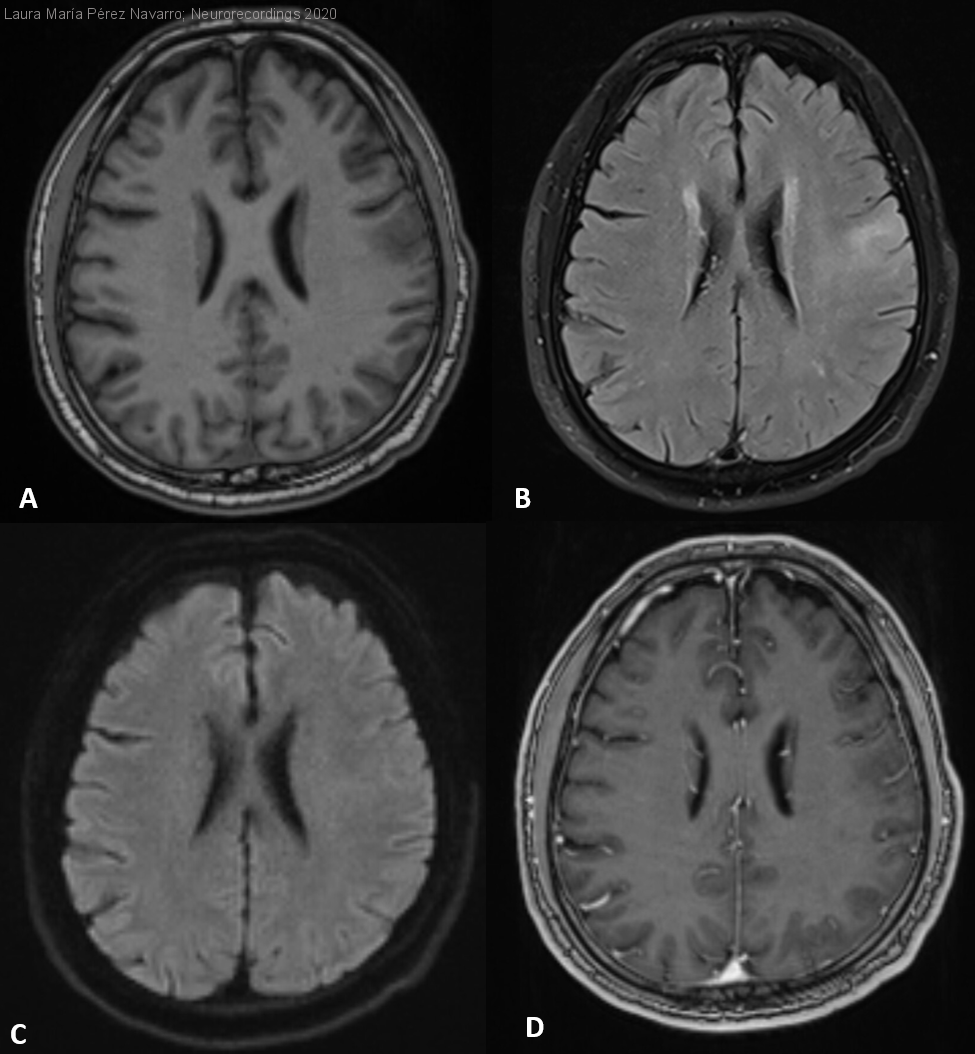

Síndrome hemisférico izquierdo agudo ¿Causa vascular o stroke mimic?

Hombre | 59 años

Diagnóstico final: Glioblastoma

Varón de 59 años, con factores de riesgo cardiovascular que, tras cuadro catarral, presenta clínica brusca de dificultad para la emisión de palabras y torpeza en extremidades derechas.

Exploración: afasia motora, parálisis facial central derecha y mioclonías...